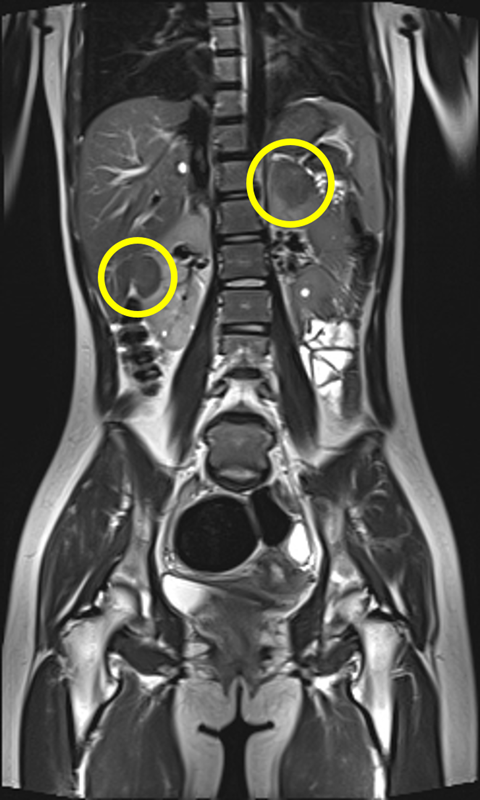

▲여러 장기에서 양성 종양이 발생하는 결절 경화증 환자의 복부 MRI 검사 사진. 양측 신장에 혈관근육지방종(노란색 표시)이 관찰되고 있다.

가장 흔한 증상인 뇌전증 발작과 피부의 혈관섬유종, 백반증을 비롯해 자폐스펙트럼장애, 인지장애, 신장 낭종, 폐세포 증식증 등 다양한 증상이 연령과 상관없이 나타나기 때문에 조기 진단과 장기적 관리가 필수적이다.